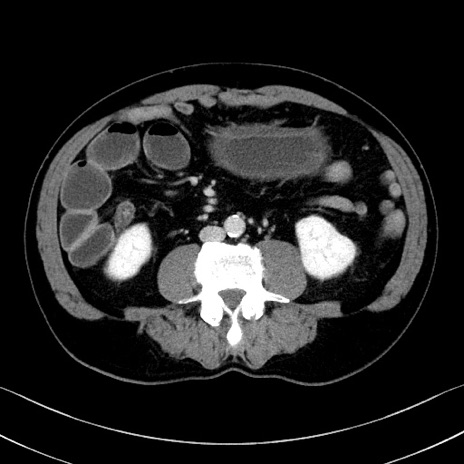

冠状断像